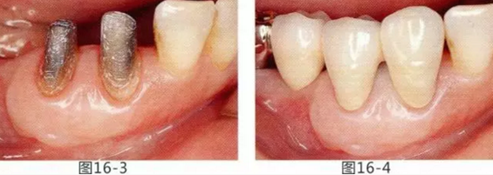

為了改善修復體周圍的環(huán)境,通過FGG(游離齦移植)來獲得附著齦的病例

有3~4mm牙周袋并且沒有附著齦的存在,系帶也在牙頸部附近位置的病例。通過FGG(游離齦移植)獲得附著齦同時切除系帶后,即使經(jīng)過了很長時間,牙齦邊緣依然保持安定的狀態(tài)。

圖16-1 右3,4牙周袋探診值為3~4mm,基本沒有附著齦。右下3部位的系帶也附著在牙頸部附近,由于清潔困難而引發(fā)了炎癥。

圖16-2 由于磨牙部缺失,為了能夠進行固定修復而在右下6位置植入種植體,制作右下3,4,5,6固定橋冠。為了增加基牙右下3,4周圍的附著齦,在實施FGG同時去除系帶。

圖16-3 獲得了足夠附著齦,可以抵抗刷牙等外部刺激。

圖16-4 獲得充分附著齦,易清潔的狀態(tài)。修復體之間的鼓形間隙大小均一也使清潔性得到提升。